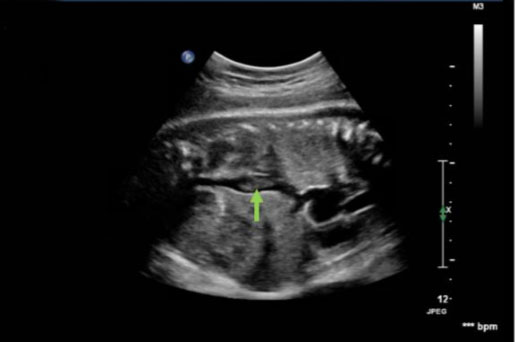

During this pregnancy, our patient was on 40 mg subcutaneous low molecular weight heparin (LMWH) daily for VTE prophylaxis due to her history of DVT and low-risk thrombophilia as well as 81 mg aspirin daily. Her first and second trimesters were uncomplicated. The patient began antenatal testing at 32 weeks of gestation, consisting of fetal heart rate monitoring and ultrasounds. Weekly biophysical profiles (BPP) were reassuring. At 32 weeks of gestation, growth ultrasound was normal, showing an estimated fetal weight of 2688 g. At 34 weeks and 3 days of gestation, her BPP was normal; however, the ultrasound showed a finding concerning for a fetal thrombosis in the IVC (Figure 1, Figure 2, Figure 3).

Figure 2: Prenatal ultrasound of sagittal fetal abdomen with inferior vena cava thrombus indicated by green arrow.